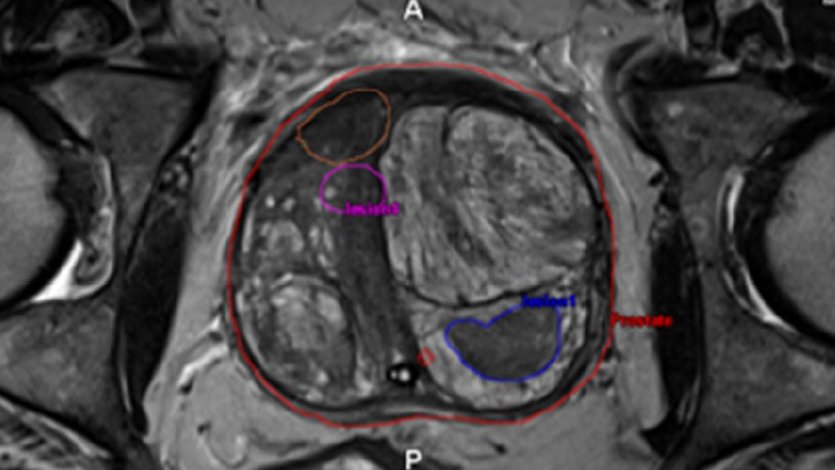

Radiology, Urology, Anatomy & Espresso Martinis.